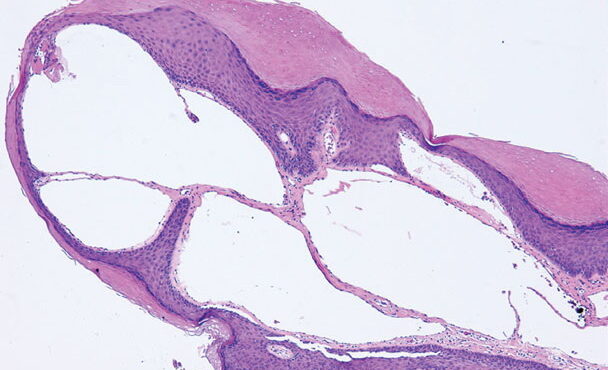

Lupus vulgaris = ุงูุฐุฃุจ ุงูุดุงุฆุน Lupus Vulgaris LV is an extremely chronic, progressive form of cutaneous tuberculosis occurring in individuals with moderate immunity and a high degree of tuberculin sensitivity. Differential Diagnosis of Tuberculosis Verrucosa Cutis ยท Warts or keratoses ยท Hyperkeratotic lupus vulgaris ยท Blastomycosis ยท Chromomycosis ยท Bromoderma ยท Lesions due to […]